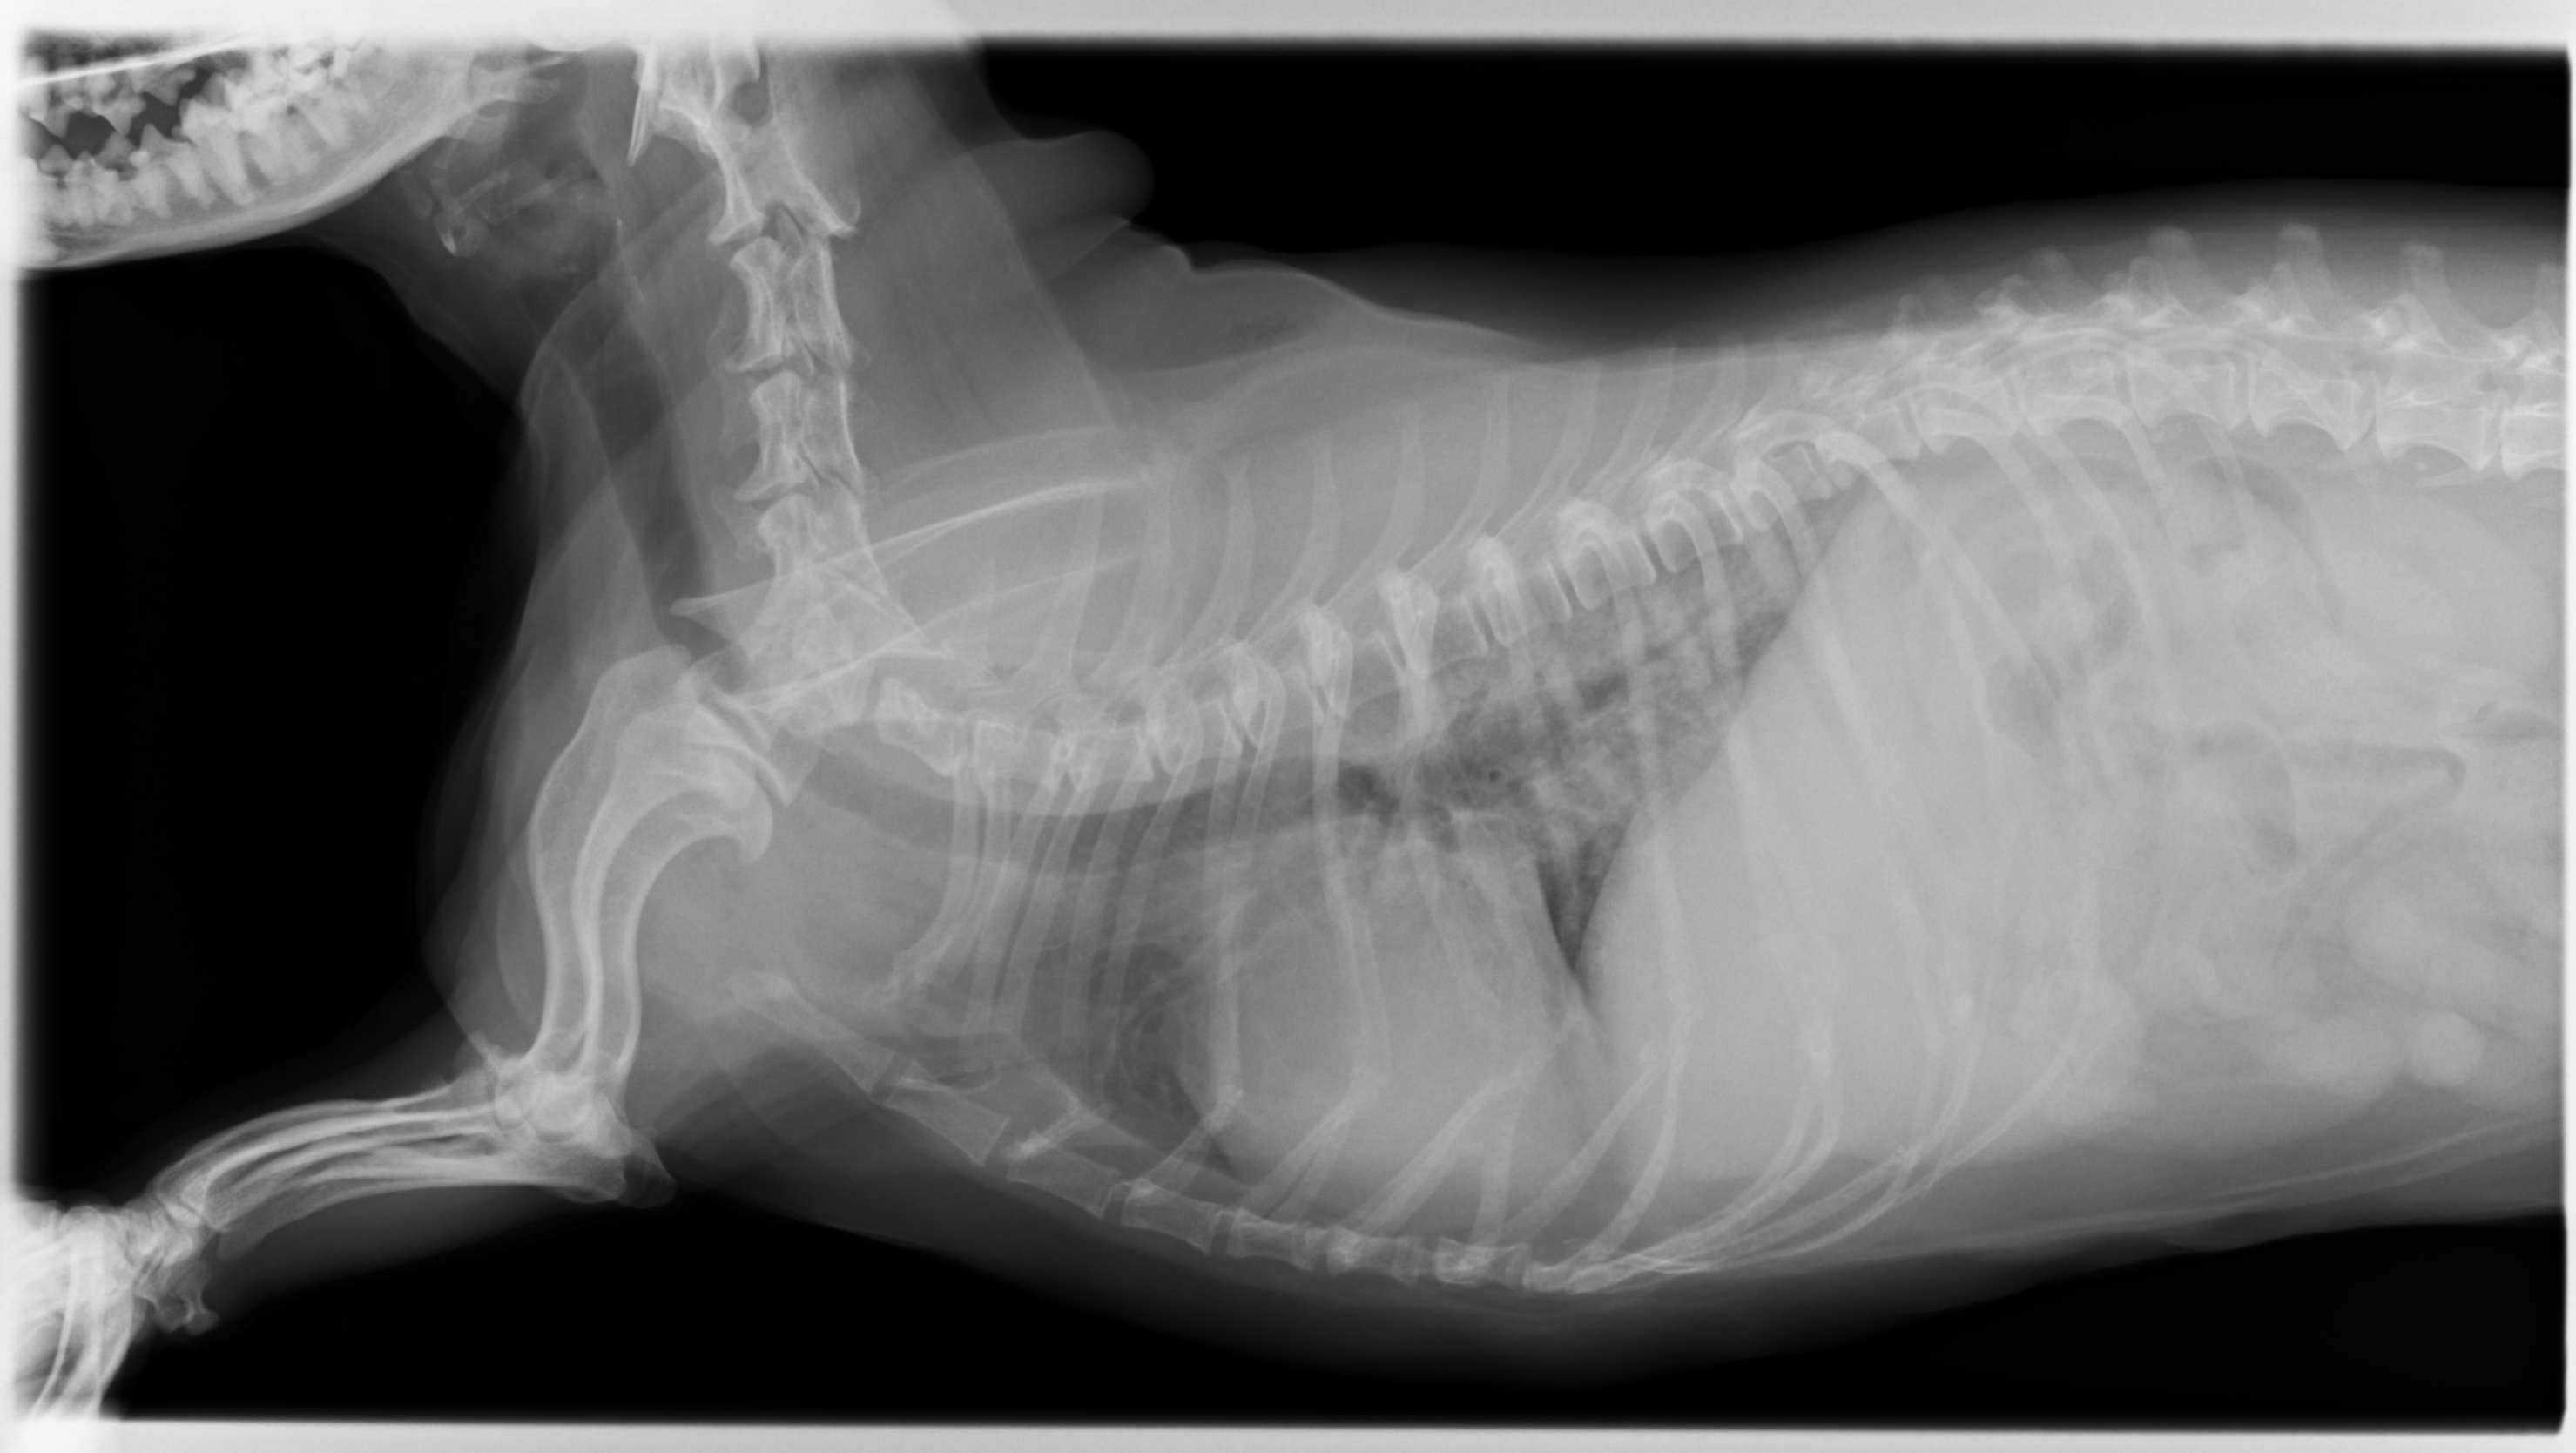

身体的検査、レントゲン検査、血液検査などから総合的に診断します。 聴診器を使って肺の音を聴診します。肺炎の場合、みずっぽいような音やゴロゴロとした異常な音が聞こえることがあります。レントゲン検査では胸部のレントゲンを撮影します。肺炎の場合、肺が白く見え、気管支が白くはっきり見えるようになります。また、左右の肺の前葉や右側の中葉といった一部の肺野が白くなっていると誤嚥性肺炎を疑います。血液検査では白血球の増加や、炎症の指標であるCRPの上昇が見られることがあり、感染の有無や炎症の程度を評価します。

レントゲン画像